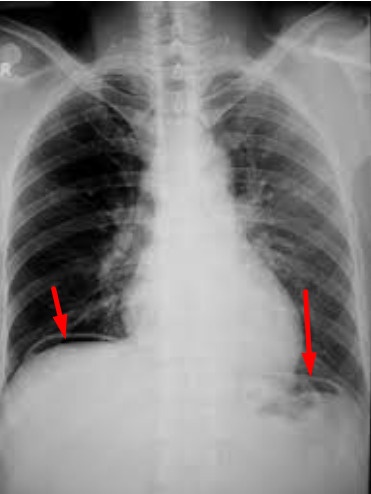

Hình khí tự do dưới cơ hoành (mũi tên đỏ) trước mổ của bệnh nhân Đ., chứng tỏ có thủng tạng rỗng (ảnh đen trắng). Ảnh thủng mặt trước hành tá tràng quan sát trong mổ của bệnh nhân Đ (mũi tên xanh). |